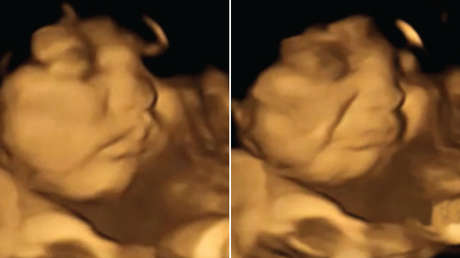

Los científicos tomaron ecografías 4D (imagen del feto en tres dimensiones en tiempo real) de 100 mujeres de 18 a 40 años, con un periodo de gestación de entre 32 y 36 semanas. Unos 20 minutos antes de cada exploración, las mujeres embarazadas habían ingerido cápsulas que contenían 400 mg de zanahoria o col rizada en polvo. Los fetos expuestos al sabor de zanahoria mostraron más respuestas de "cara de risa", mientras que los expuestos al sabor de col rizada mostraron más respuestas de "cara de llanto". La exposición a solo una pequeña cantidad de estos vegetales fue suficiente para estimular una reacción de disfrute o desagrado hacia estos alimentos.

La Dra. Beyza Ustun, de la Universidad de Durham, quien dirigió la investigación, expresó en un comunicado difundido el miércoles, que las madres podrían prevenir en sus hijos los comportamientos "quisquillosos" con la comida al comer bien durante el embarazo. "Fue realmente sorprendente ver la reacción de los bebés nonatos a los sabores de col rizada o zanahoria durante los escaneos y compartir esos momentos con sus padres", dijo.